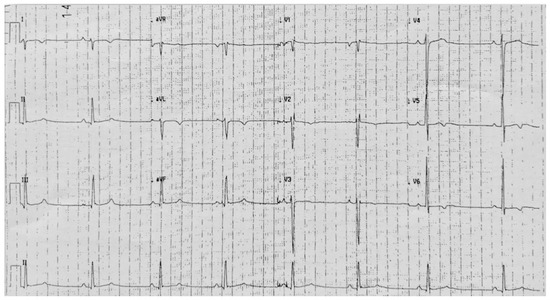

5. Case 4